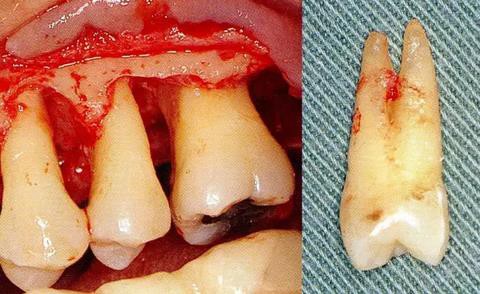

▼圖6-4 下頜第二后磨牙的融合根。在根尖的組合部的產(chǎn)生了附著喪失,導(dǎo)致急速惡化。

[第一前磨牙的根分叉部病變]

▼圖6-5 上頜磨牙部的骨組織缺失。由于左側(cè)第一前磨牙遠中部的垂直骨組織缺失,導(dǎo)致拔牙。這顆第一前磨牙多數(shù)情況下都是2根分叉,根干很長。所以,這種狀態(tài)下露出根分叉部的話,就不得不進行拔牙。